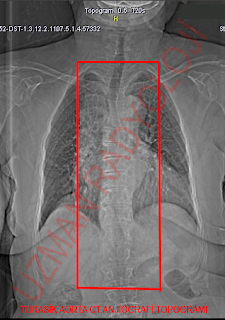

AORTA CT ANJİOGRAFİ PROTOKOL

Anevrizma, istmus stenozu, muhtemel diseksiyon durumlarında endikedir. Scan delay (sec): Gecikme zamanı -Standart gecikme zamanı 20-30 sn dir. -Bolus tracking mutlaka kullanılmalıdır. ROI: Desenden aorta, treshold 100 HU. 3D teknikleri: -VRT/MIP: koronal ve sagital. IV contrast miktarı (volume): -100-120 cc 350 ve 320 lik Injection rate (injeksiyon hızı) -4 cc/sec:sn: mümkünse sol antekübital venden verilmelidir. Topogram: anterioposterior , FOV : Supraklavikular-simfizis pubis kaudali İmajlar kraniokaudal elde olunmalıdır. |